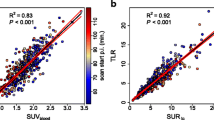

According to the RECIST criteria as applied on CT we identified 8 responders and 11 non-responders. SAM1 and ΔSAM values for responders versus non-responders were 57 (SD 119) versus 297 (SD 625) for SAM1 (p = 0.2) and 99 % (SD 3 %) versus 32 % (SD 44 %) for ΔSAM (p = 0.001), respectively. The area under the ROC curve (AUC) for SAM1 and ΔSAM were 0.74 and 1.0, respectively, suggesting that ΔSAM may accurately assess response to treatment of liver metastases in patients suffering from colorectal cancer (CRC) (see Fig. 2). Using a cutoff of 85 % reduction for ΔSAM, responders could be separated from non-responders with a sensitivity of 100 % and a specificity of 100 %.

SUVmax1 and ΔSUVmax values in responders versus non-responders were 3.9 (SD 2.4) versus 6.3 (SD 3.1) for SUVmax1 (p = 0.08) and 94 % (SD 17 %) versus 7 % (SD 40 %) for ΔSUVmax (p = 0.0001), respectively. The AUC for SUVmax1 and ΔSUVmax were 0.79 and 0.99, respectively, suggesting that ΔSUVmax may accurately assess response to treatment of liver metastases in patients suffering from CRC (see Fig. 2). Using a cutoff of 48 % reduction of ΔSUVmax, responders could be separated from non-responders with a sensitivity of 100 % and a specificity of 91 %.

The AUC of ΔSAM and ΔSUVmax proved to be not significantly different (p = 0.6).